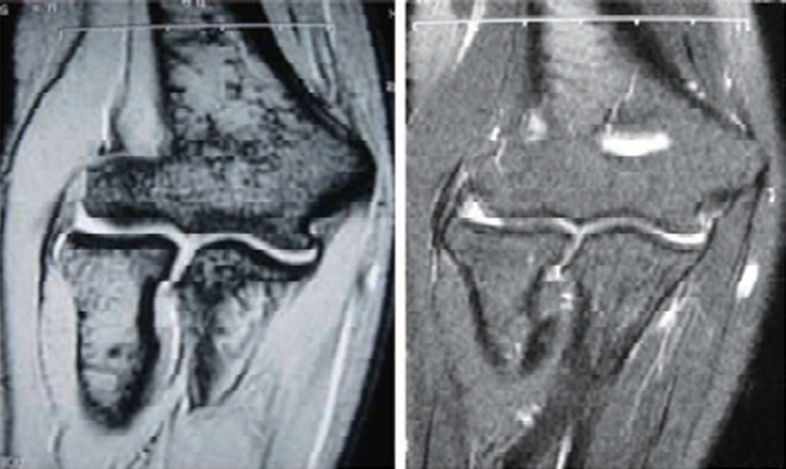

(2)MRI检查MRI检查可见T1和T2信号增强,提示肌腱肥厚。部分患者合并出现关节积液、肱桡关节滑膜增生等表现。